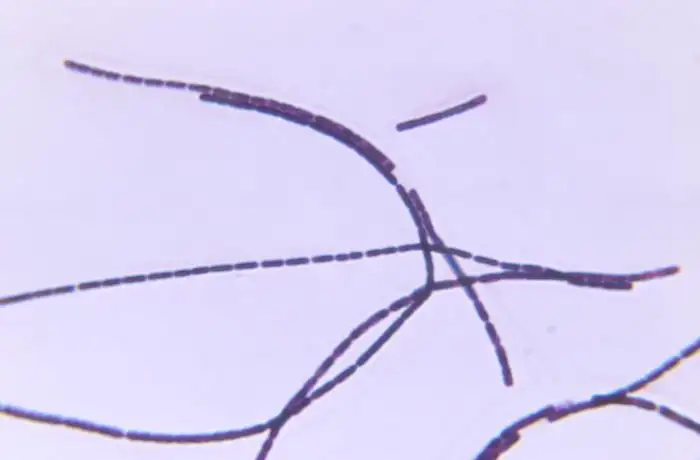

在接下来的几个月里,这位乡村医生完成了一系列足以改变医学史的实验。他从病死牛的血液中分离出一种杆状细菌,将其培养在自制的培养基上,然后用培养出的细菌感染健康的小鼠和兔子。结果令人震惊:所有被接种的动物都在几天内死亡,它们的血液中充满了同样的杆状细菌。这是人类历史上第一次,某种疾病的具体致病菌被明确鉴定出来。

科赫的发现远不止于此。他观察到这种细菌在恶劣环境下会形成一种特殊的结构——孢子。这些孢子能够在体外存活极长时间,一旦进入合适的宿主体内,便会"苏醒"并开始繁殖。这一发现解释了为什么炭疽会在某些牧场反复爆发:那些休眠在土壤中的孢子,可以等待数年甚至数十年,直到有不幸的动物将它们唤醒。